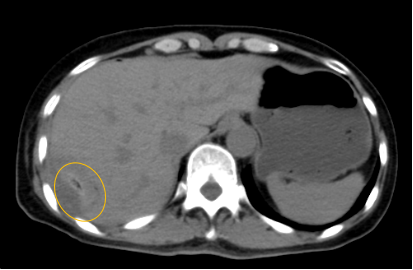

入院后,影像診療中心立即給李女士完善了CT和MR檢查,發(fā)現(xiàn)病變位于肝包膜下,臨近膈肌,消融治療過程中有并發(fā)損傷膈肌的可能,難度較大,但是采用精準(zhǔn)影像定位是可以完成的。陳寶瑩主任立即與腫瘤三病區(qū)劉金鵬主任聯(lián)系,并與影像微創(chuàng)治療小組進(jìn)行MDT討論:患者為卵巢癌肝右葉包膜下單發(fā)轉(zhuǎn)移瘤,最長(zhǎng)徑不超過3cm,患者對(duì)局部治療的主觀愿望強(qiáng)烈,符合消融治療專家共識(shí),遂制定了影像引導(dǎo)下局部消融治療聯(lián)合全身治療的綜合治療方案。

針對(duì)這個(gè)特殊部位的腫瘤,要想消融完全,那么膈肌損傷的風(fēng)險(xiǎn)就很高,陳寶瑩主任帶領(lǐng)影像微創(chuàng)亞專業(yè)組成員仔細(xì)閱讀CT圖像,設(shè)計(jì)進(jìn)針路徑,結(jié)合MR圖像確定腫瘤活性范圍,制定了周密而詳盡的消融計(jì)劃。臘月二十九,即住院第二天影像微創(chuàng)治療小組圓滿為患者完成了腫瘤微波消融治療,觀察24小時(shí)后出院回家過年。術(shù)后48小時(shí)隨訪患者無明顯不適,術(shù)后7天隨訪,患者肝功、血常規(guī)等各項(xiàng)指標(biāo)均恢復(fù)正常。